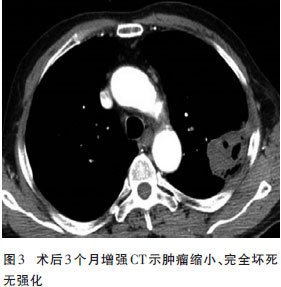

经皮盐酸注射适用于孤立小肝癌,尤其适于治疗具有包膜的直径小于5 cm的肝癌(图3)。

http://webres.medlive.cn/upload/000/025/837

研究表明,在注射复方消融合剂后,其消融作用向周围逐渐扩散,持续约6小时。注射后24~72小时行CT平扫,显示注射部位为高密度造影剂填充区,其间有少量气化灶,病灶周边呈低密度改变,强化扫描示低密度区域无血管分布,穿刺活检病理检查示病灶全部为坏死组织,正电子发射体层摄影(PET)-CT检查治疗区域无代谢信号。3~6个月后,消融区域逐渐缩小,甚至消失。

直径≤3.0 cm的孤立性肿瘤均在治疗1~2次后完全性坏死。单发肿瘤直径≤3.0 cm的患者,治疗后的1、2、3年生存率分别为100%、90%和85%,多发肿瘤患者的1年生存率可达87.5%。